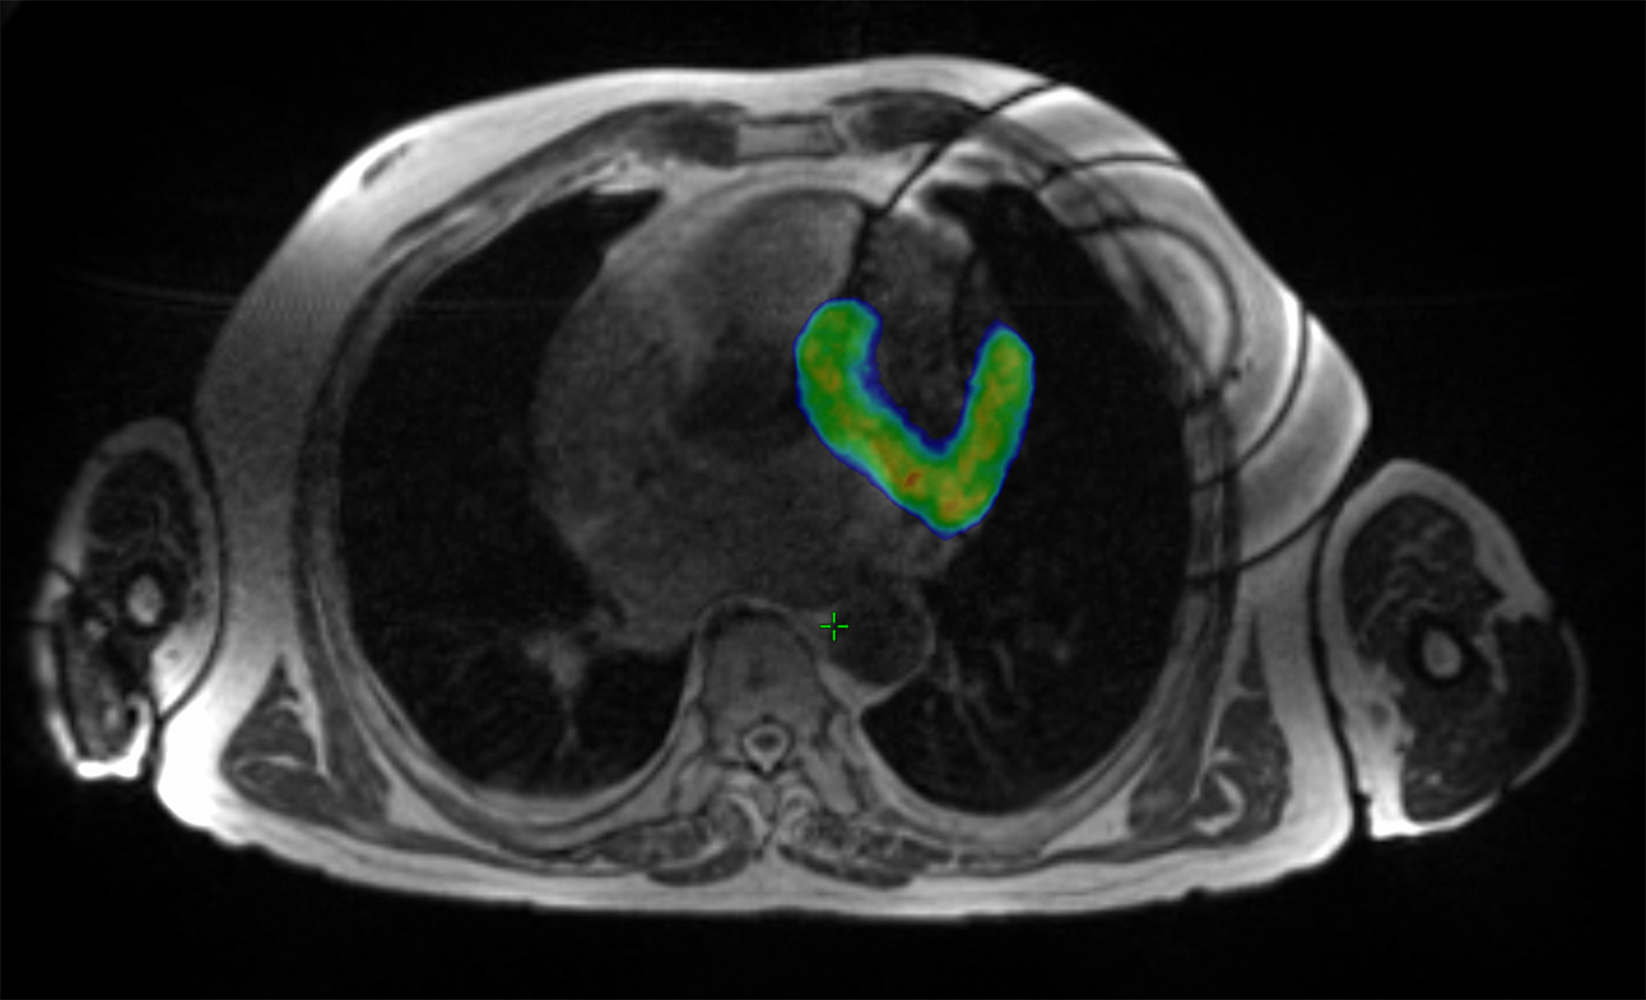

Seit April 2019 können in der Klinik für Radio-Onkologie am USZ Patientinnen und Patienten an einem MRI-Linac-Gerät behandelt werden. «Mit diesem Linearbeschleuniger können wir vor und während der Bestrahlung durch MR-Bildgebung jedes Ziel im Körper eines Patienten verfolgen und die Bestrahlung in Echtzeit steuern und anpassen», erklärt Dr. Tanadini-Lang, Leitende Physikerin der Klinik für Radio-Onkologie. Die Bestrahlung kann damit noch präziser erfolgen.

«Ursprünglich wurde diese neue Technologie für die Krebsbehandlung entwickelt», erklärt Prof. Matthias Guckenberger, Direktor der Klinik für Radio-Onkologie. «In einem Kooperationsprojekt der Klinik für Kardiologie, des Instituts für Diagnostische und Interventionelle Radiologie und der Klinik für Radio-Onkologie wurde die MRI-Linac-Technologie am USZ nun erstmals für eine sogenannte Radioablation zur Behandlung eines Patienten mit wiederkehrenden, lebensbedrohlichen Herzrhythmusstörungen eingesetzt.» Bei diesem Verfahren wird das für die Rhythmusstörung verantwortliche Areal des Herzmuskels gezielt bestrahlt.